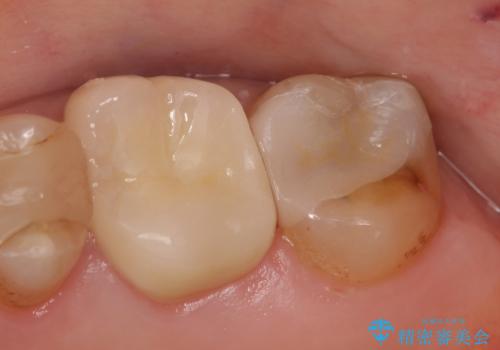

左上6番目は銀歯・虫歯を除去後、オールセラミッククラウンにて補綴を行いました。

左上7番目も虫歯だったため、銀歯・虫歯を除去後、セラミックインレーにて修復を行いました。

今回用いたオールセラミッククラウンはジルコニアフレームという白い素材の上にセラミックを盛っているため、審美性が非常に高いのが特徴です。

また、ジルコニアは人工ダイヤモンドの材料にも使われているほど高い強度を持っており、そのためオールセラミッククラウンは審美性だけでなく、奥歯やブリッジの補綴も可能とするクラウンです。

当院のセラミックインレーはemaxという強度と審美性に優れた材料を使用しています。

またプレス方式でインレーを製作しているため、削り出しで製作するCADCAMより優れた適合性も持ち合わせており、虫歯が再発しにくい修復物です。